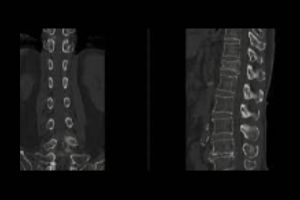

A CT scan bilateral sacroiliac joint (also known as bilateral sacroiliac joint imaging) is a medical procedure that uses X-ray technology to create cross-sectional images of the sacroiliac joints. By offering high-resolution images, this procedure allows healthcare providers to closely examine the bones, cartilage, and surrounding tissues of the SI joints. The use of contrast dye can help make the images clearer, allowing doctors to find conditions like fractures, arthritis, and swelling more easily. It is often suggested when X-rays or MRIs are not enough to identify specific issues with the sacroiliac joints.

- Scanning: You’ll lie on a table that moves into the CT scanner. The machine will rotate around your body to take cross-sectional images of your sacroiliac joints.